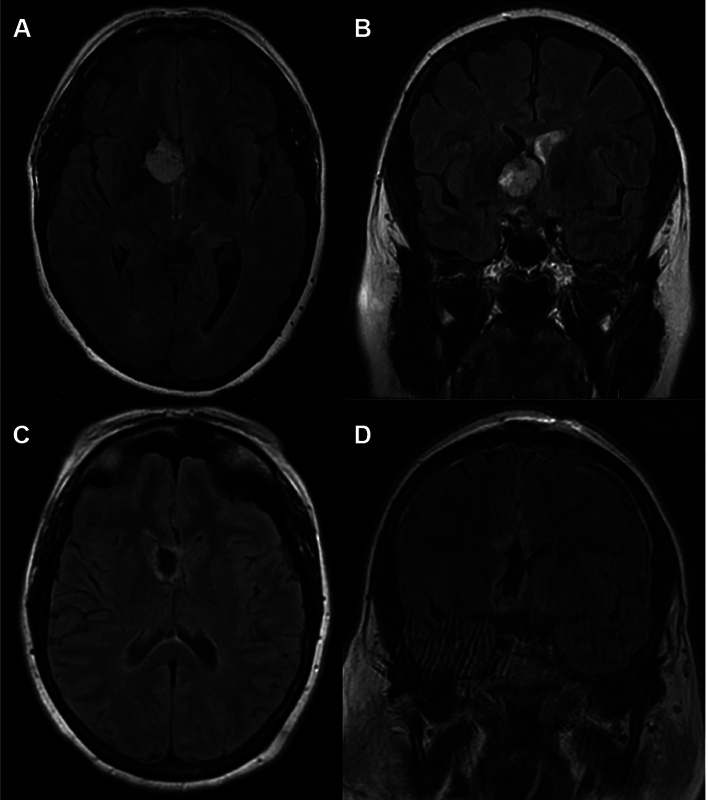

背景:室管膜下巨细胞星形细胞瘤(SEGA)是一种发生于室管膜下组织的罕见肿瘤。SEGA主要与结节性硬化症(TSC)相关,可表现为一系列不同的症状,最常见的是癫痫发作或TSC的神经皮肤特征。我们提出一个新病例散发性SEGA在一个59岁的妇女谁提出了急性肝实质内出血(IPH)。方法系统查阅文献,结合案例分析。结果1例59岁女性患者表现为头痛,意识水平下降,急性IPH累及前隔透明膜和右侧内侧尾状头。MRI提示有潜在的肿瘤,后续影像学显示肿瘤生长缓慢,需显微手术切除。术后病理证实SEGA (WHO I级),无TSC1/2突变。随访1年,患者无疾病,神经功能完整。一项系统综述确定了7篇出版物,在9名无TSC的成年患者中病理证实了SEGA。头痛、乳头水肿和视觉障碍是最常见的症状。治疗方案包括显微手术切除与活检后的放射学监测,截至最后一次随访,总体无症状生存率至少为80%。结论:我们报告了第10例散发性SEGA成人患者,无TSC,并对这种罕见的肿瘤实体进行了相关的系统回顾。需要进一步的研究来确定散发性SEGA发展的危险因素,以及可能偏离儿童TSC患者标准方案的这种疾病管理的潜在途径。

Background  Subependymal giant cell astrocytoma (SEGA) is a rare neoplasm arising from subependymal tissue. Predominantly associated with the tuberous sclerosis complex (TSC), SEGA may present with a range of diverse symptoms, most commonly seizures or neurocutaneous features of TSC. We present a novel case of sporadic SEGA in a 59-year-old woman who presented with acute intraparenchymal hemorrhage (IPH). Methods  Systematic literature review and illustrative case example. Results  A 59-year-old woman presented with a headache decreased level of consciousness, and acute IPH involving the anterior septum pellucidum and right medial caudate head. MRI was concerning for an underlying neoplasm, which grew slowly on follow-up imaging, prompting microsurgical resection. A gross total resection was achieved, and postoperative pathology confirmed SEGA (WHO grade I) without TSC1/2 mutation. She remained disease-free and neurologically intact at 1-year follow-up. A systematic review identified seven publications that revealed pathologically confirmed SEGA in nine adult patients without TSC. Headache, papilledema, and visual disturbances were the most common presenting symptoms. Treatment protocols included microsurgical resection versus biopsy followed by radiographic surveillance, and the overall rate of symptom-free survival was at least 80% as of the last follow-up. Conclusion  We report the tenth case of sporadic SEGA in an adult patient without TSC, as well as an associated systematic review of this rare neoplastic entity. Further study is required to identify risk factors for the development of sporadic SEGA, as well as potential avenues for the management of this disease that may depart from the standard protocol in pediatric TSC patients.